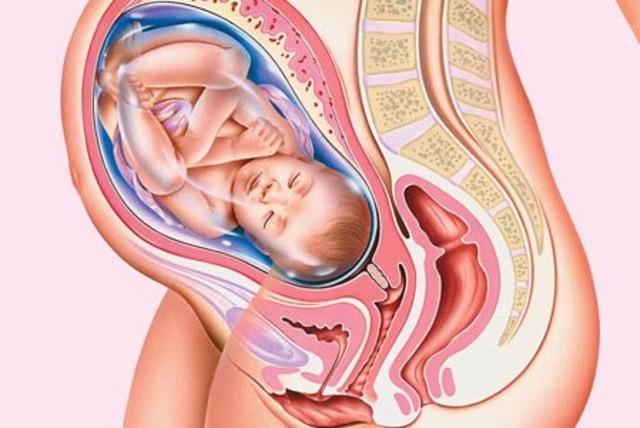

• 28a SEMANA-SEPTIMO MES

28a SEMANA-SEPTIMO MES

El feto pesa entre 1000 gramos y 1300 gramos. Las arrugas de la piel comienzan a desaparecer, pues se deposita tejido graso debajo de la dermis. El cabello es más largo que los del resto del cuerpo. Los bordes de los párpados, unidos desde el tercer mes, se separan. Los pulmones comienzan a adquirir movimientos respiratorios.

El sistema nervioso central puede regular la temperatura y los movimientos respiratorios, lo que es de importancia en el caso de que se adelante el parto, porque el bebé tendrá posibilidades de vivir. Generalmente se encuentra con la cabeza para abajo (posición cefálica).